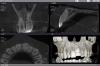

Палыч Опубликовано 16 мая, 2008 Поделиться Опубликовано 16 мая, 2008 А это каково Ссылка на комментарий

Большой Зеленый Опубликовано 16 мая, 2008 Поделиться Опубликовано 16 мая, 2008 Я думаю, на такой зуб с перфорацией МК ставить категорически нельзя! Зуб безнадежно испорчен. Удалять и не мучать ни себя, ни пациента.А где вы там перфорацию увидели? Нету там никакой перфорации .Вовремя остановились <_> А это каковоДа тоже веселенький зубчик Ох Анроша прошу пардону .Торможу.. Ссылка на комментарий

DAURIA Опубликовано 16 мая, 2008 Поделиться Опубликовано 16 мая, 2008 А это каковобольно смотреть! пришла пациентка, боли только усилились. хирурги искоренили причину радикально((("Резать к чертовой матери! Не дожидаясь перитонита!»" Ссылка на комментарий

Палыч Опубликовано 17 мая, 2008 Поделиться Опубликовано 17 мая, 2008 Доктор, кто его так? С велика упал. Ссылка на комментарий